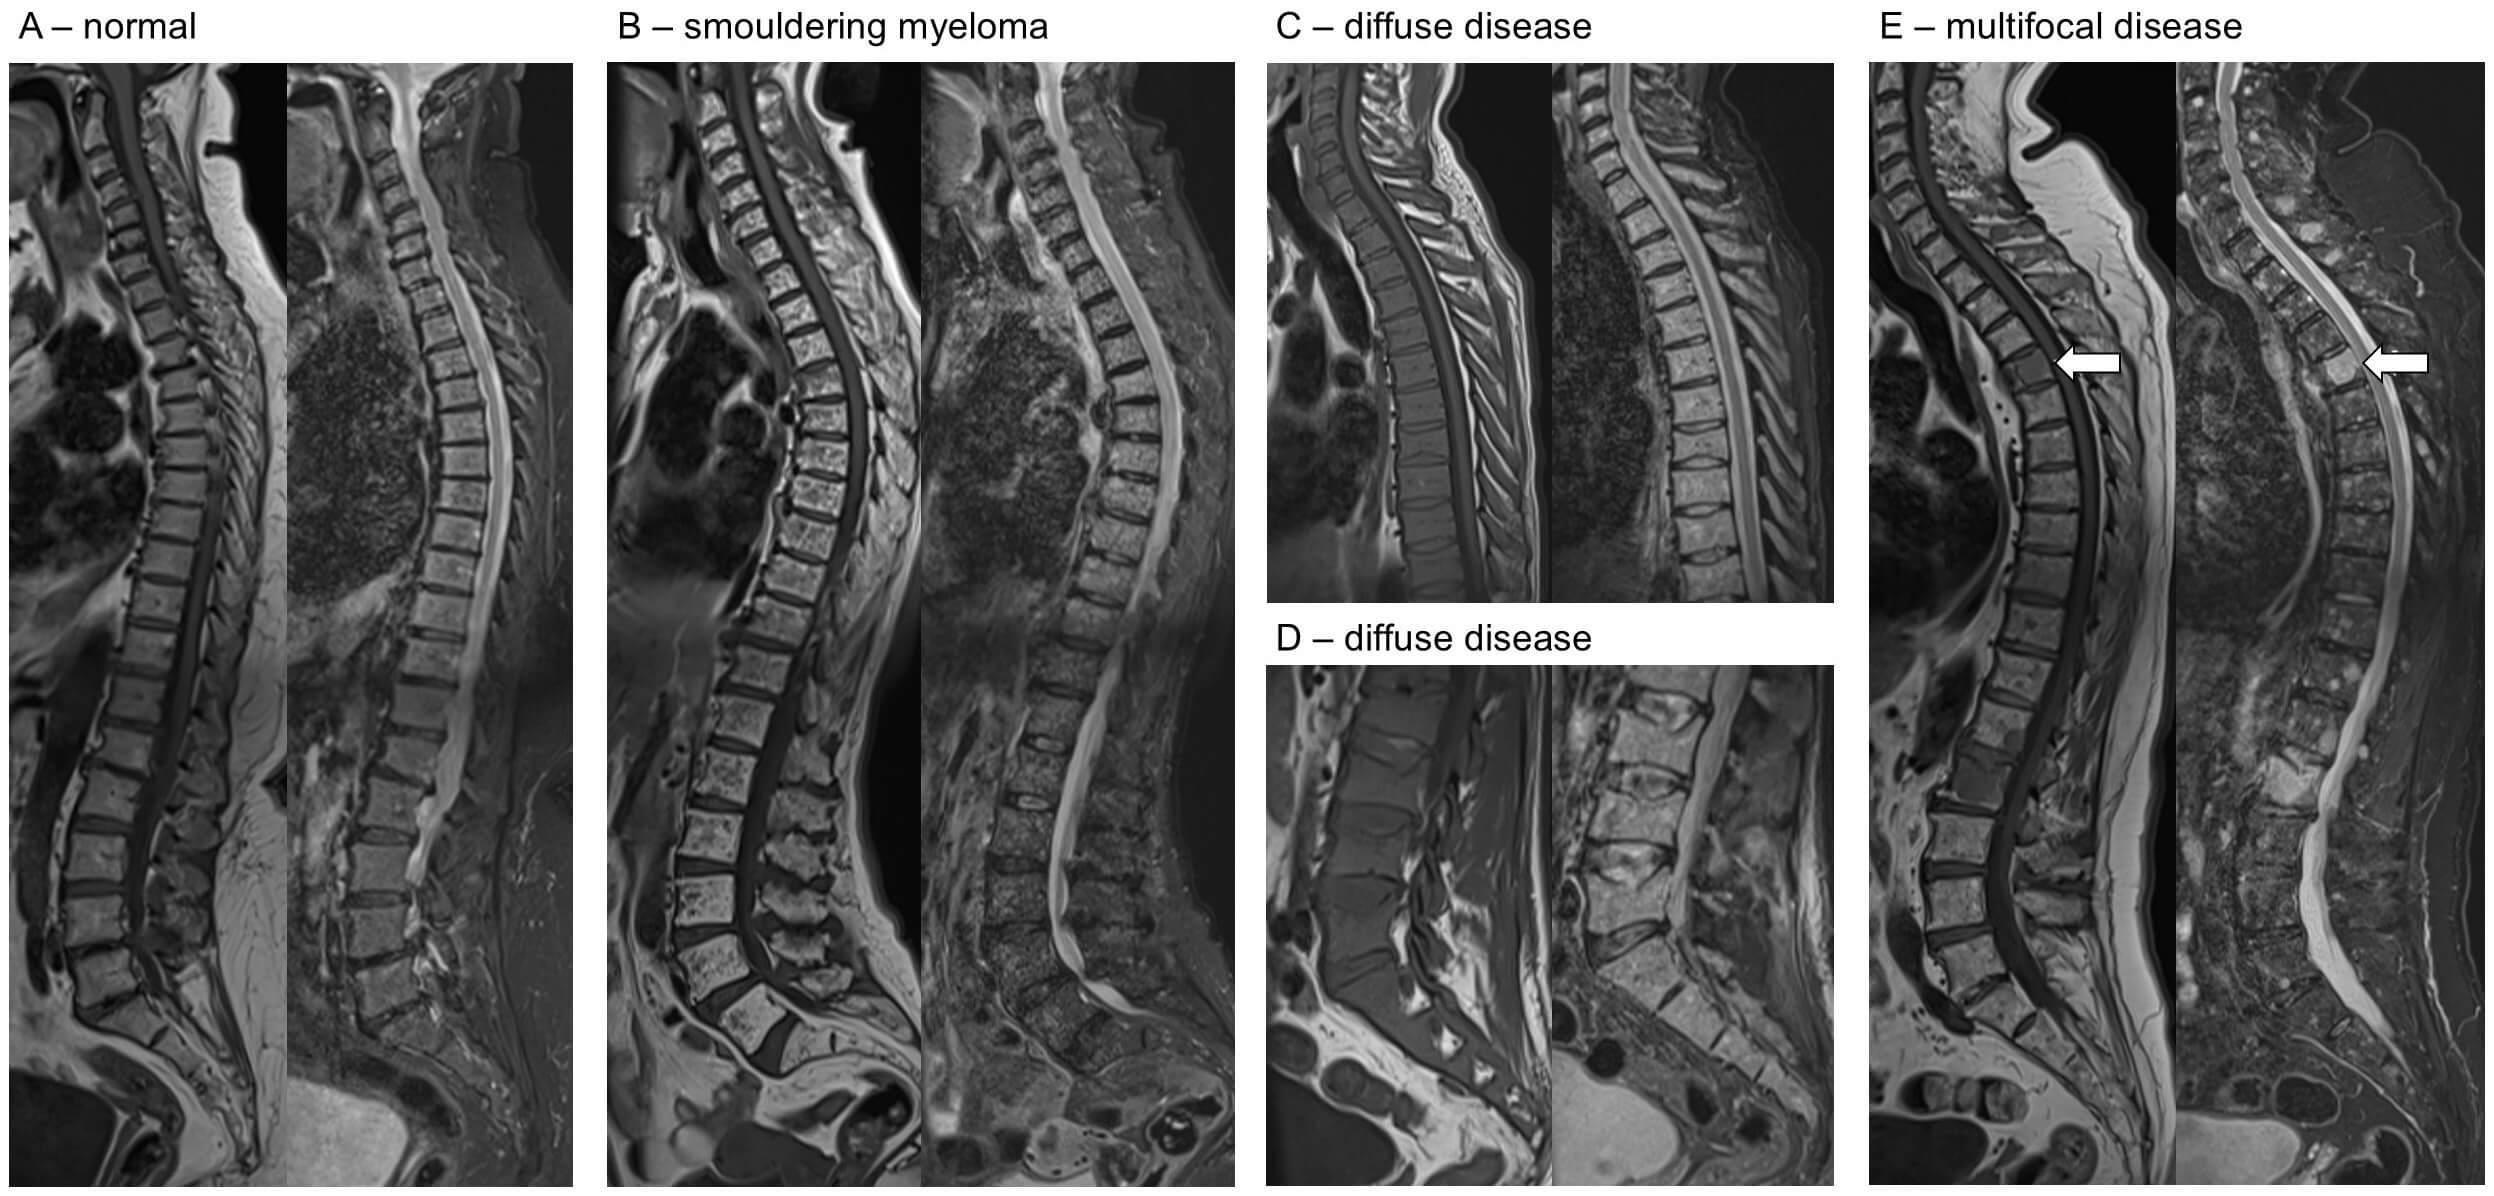

Fig. 2.

Example MRI images across the spectrum of disease. For each pair of images, T1 sequences are on the left, short tau inversion recovery (STIR) on the right. (A) Normal T1 sequences are fat sensitive, and bone marrow is bright. STIR sequences are fluid-sensitive fat fat-saturated. (B) Smouldering myeloma, with innumerable small foci seen on T1 (low signal, pepper) and STIR (high signal, salt) throughout the spine, but not reaching the diagnostic threshold for myeloma. (C,D) Diffuse disease is shown by reduced marrow signal on T1 and increased signal on STIR (C, thoracic; D, lumbar). (E) Multifocal disease identified by hypointense areas on T1 with corresponding increase in signal in STIR sequences (e.g., as identified by the arrows).